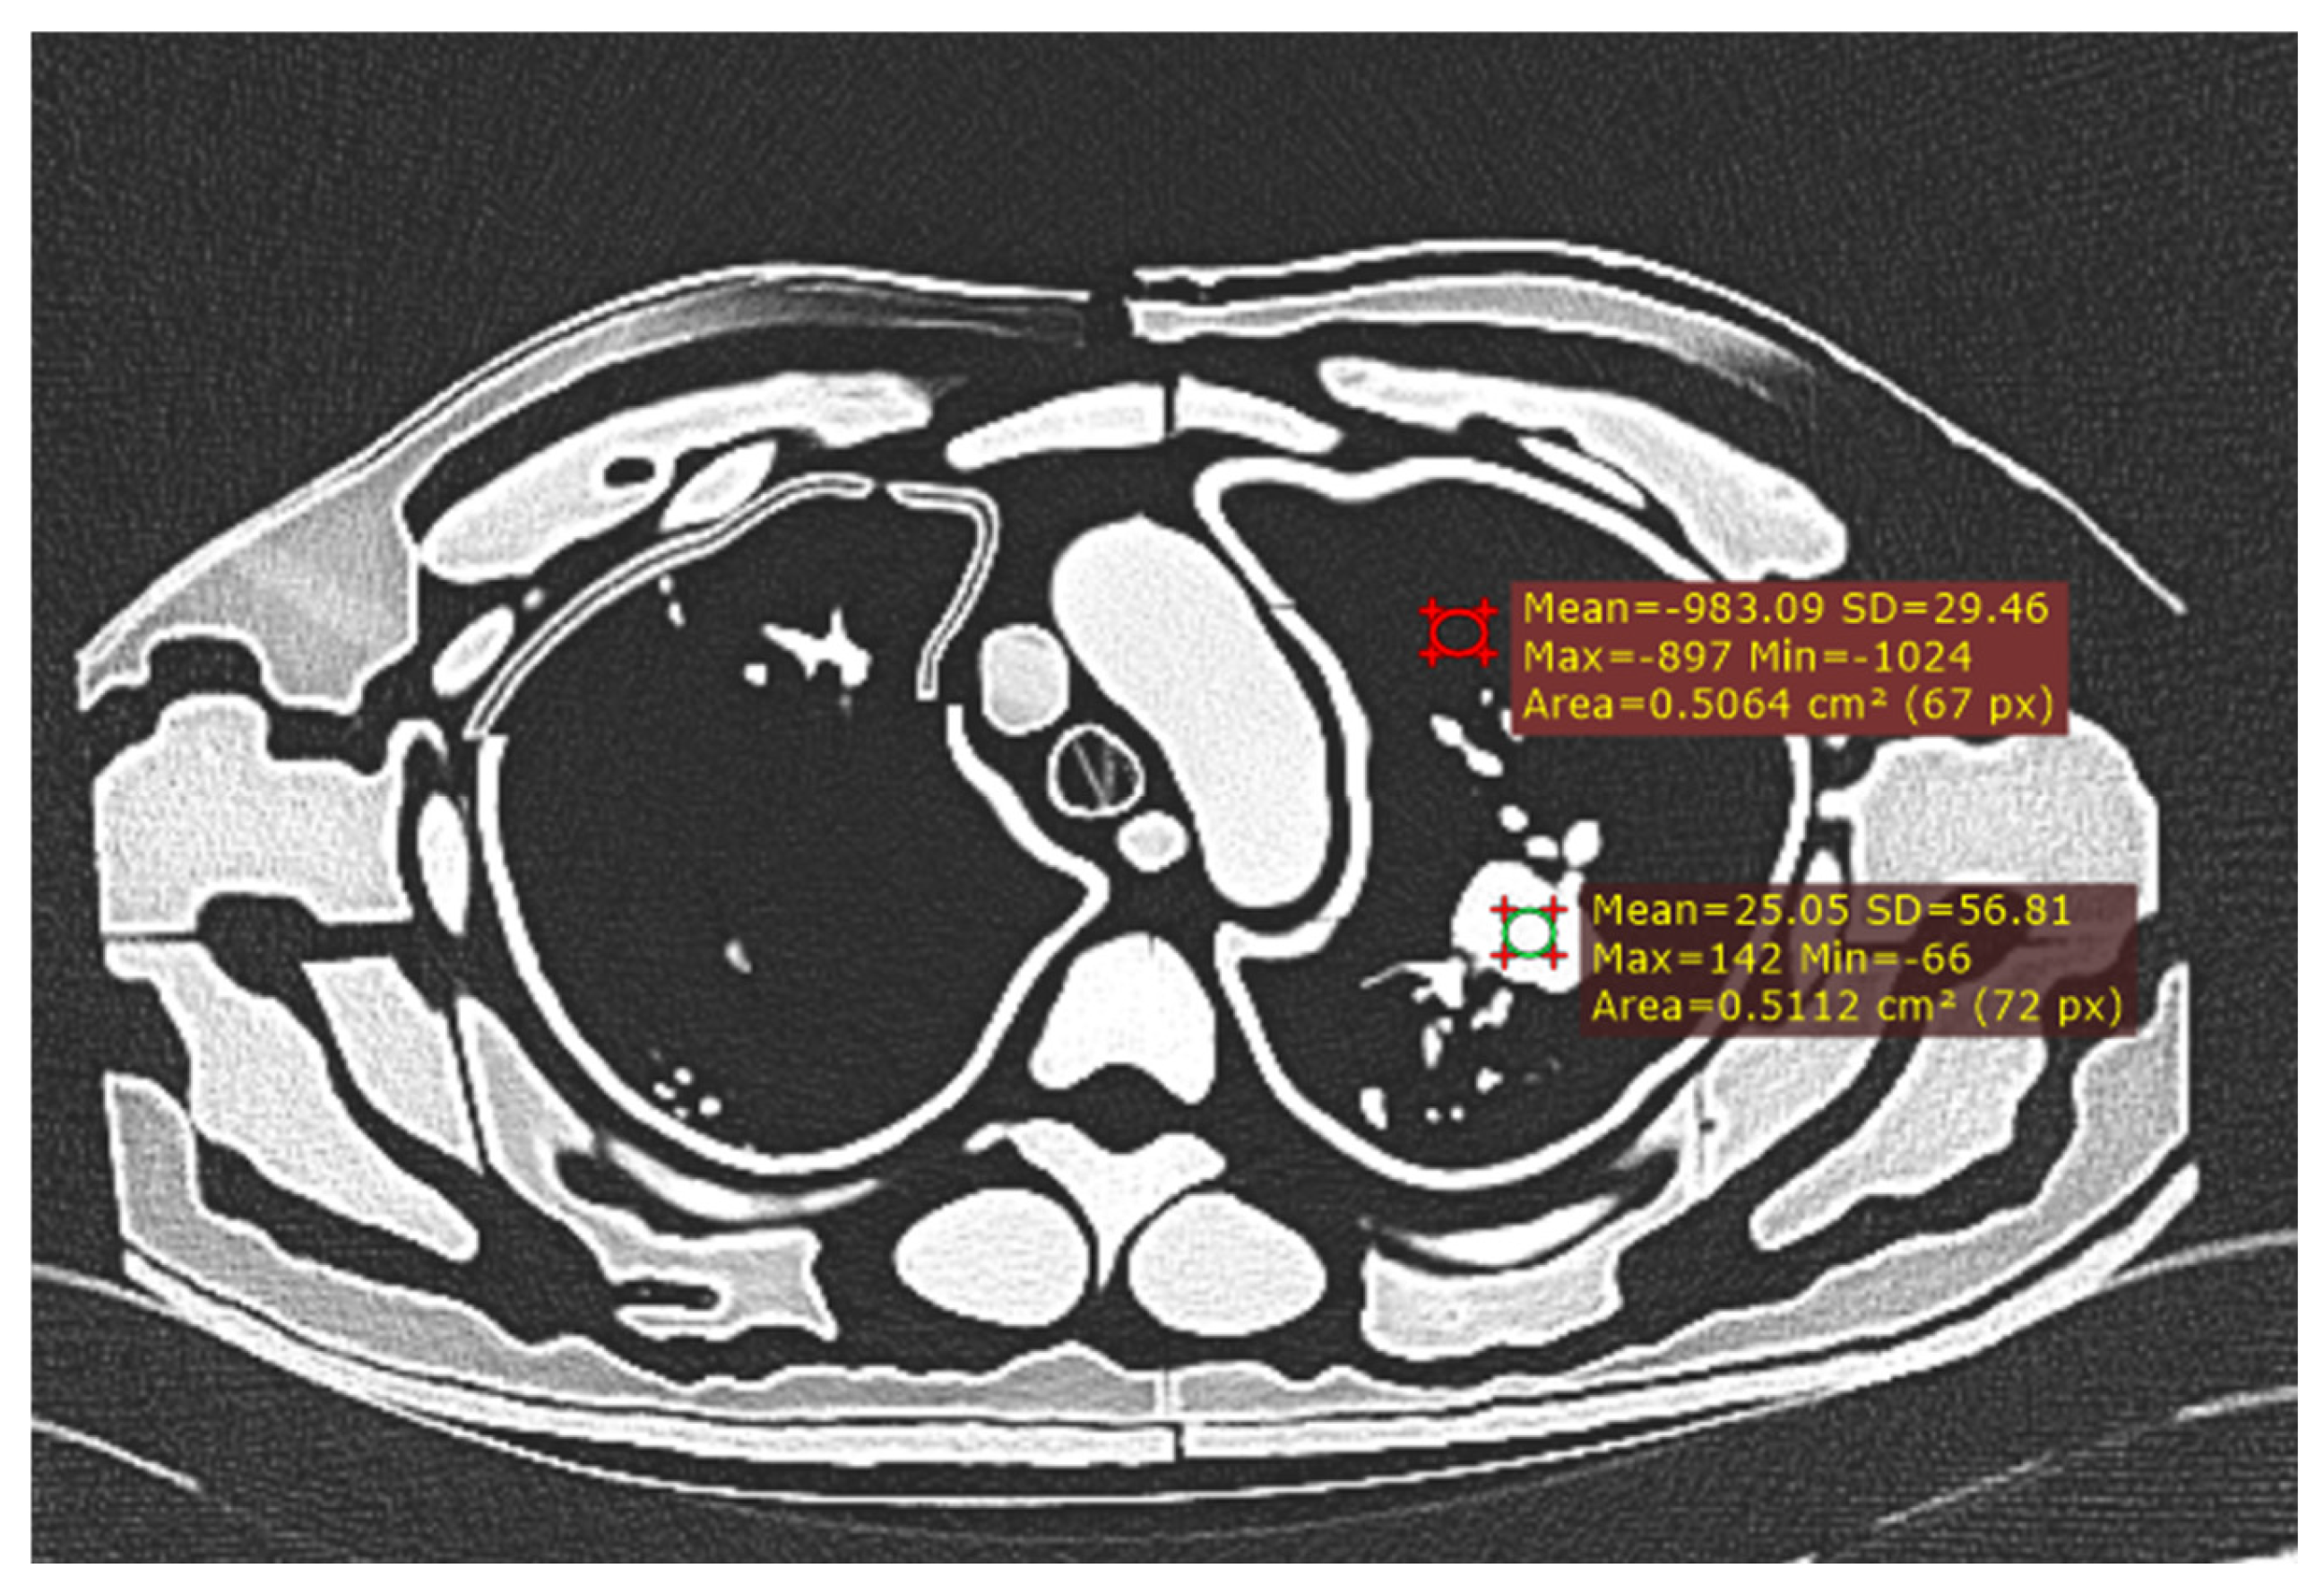

Figure 3. Measurement of CNR with ROI in largest nodule and background lung tissue.

Mean HU and noise were measured using Radiant DICOM viewer (version 2023.1) by drawing a circular 0.5 cm2 region of interest (ROI) in the biggest lung nodule. Standard deviation of the measured HU represents the image noise [17].

CNR = M e a n   H o u n s f i e l d   U n i t H U   n o d u l e M e a n   H U   b a c k g r o u n d   l u n g I m a g e   N o i s e

The mean HU was measured in the biggest nodule compared to the background lung tissue, taking care to avoid surrounding vessels. Image noise was calculated as the standard deviation from a 0.5 cm2 ROI in the lung tissue [34].